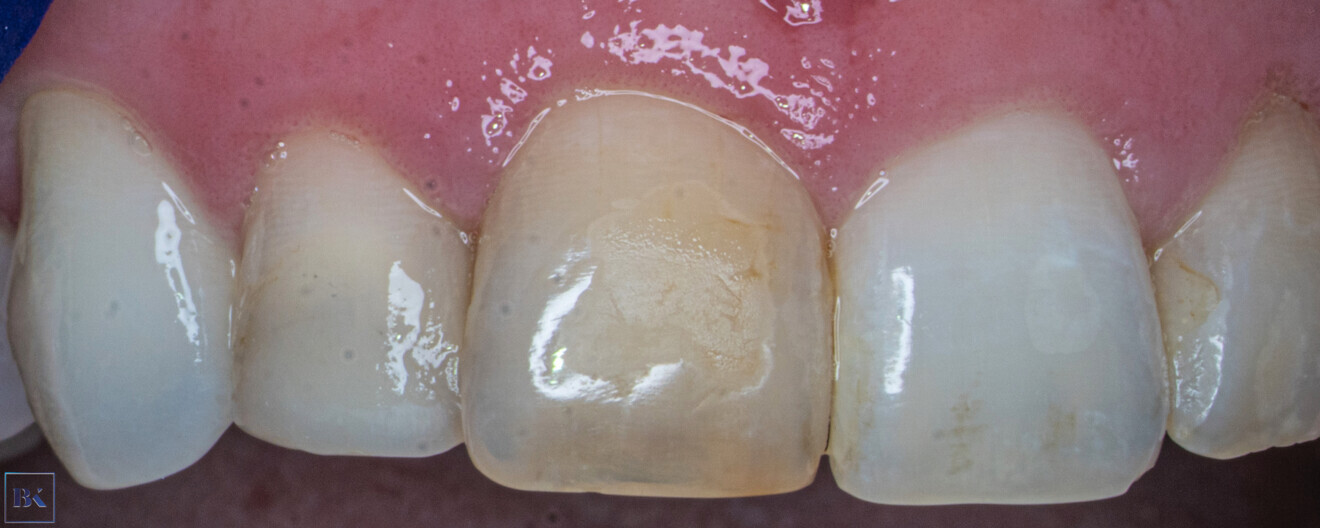

Jacobsen and Kerekes report that, although PCO necrosis and periapical disease are rare, they can occur after many years after the trauma. Bastos and Cortes emphasise that crown discoloration can be present in many cases and can be a first visible factor of PCO. Usually, the colour changes to dark yellow or even grey.

A 30-year-old female patient presented to the dental clinic complaining of constant pain of the left central incisor. Moreover, the patient was unhappy with the aesthetics of both incisors and had a history of trauma (Fig. 14). CBCT examination was performed with the 9000 C 3D (Fig. 15). The CBCT scan revealed a periapical lesion around the left central incisor and PCO for 12 mm from the incisal edge. The root of the left incisor was approximately 5 mm shorter than the root of the right incisor, which could indicate apical inflammatory root resorption. Moreover, PCO was present in the right central incisor up to 12 mm from the incisal edge, and an irregular shadow in the central area of the root was present. This image could indicate internal resorption. There was no lesion in the periapical area. In both teeth, the size of the canals in the periapical area were narrower than the typical size of the canals in the central incisors.

Fig. 14: Intra-oral view of the initial situation. Visible discoloration of the right central incisor.